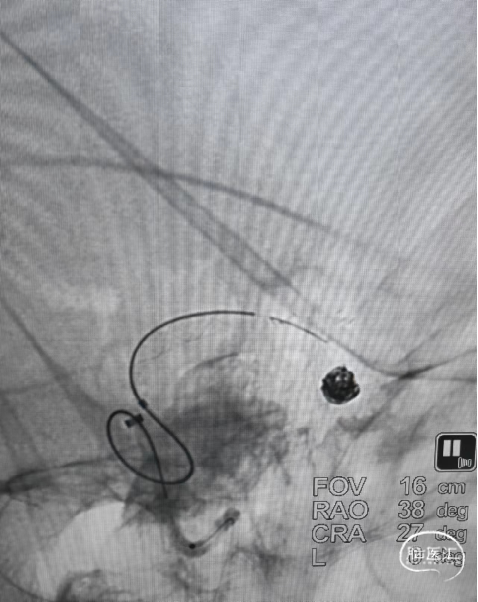

随即进行颈内动脉末端夹层动脉瘤的治疗,工作位置角度下,交换XT-27支架微导管,通过辅助支架至大脑中远端。

沿支架微导管输送Nuva®血流导向密网支架,待支架头端显影点与微导管齐平,支架输送到位,整体回撤微导管和支架至合适的锚定位置,在大脑中M1中段原位释放密网支架。

支架顺利打开,造形可见支架贴壁良好。